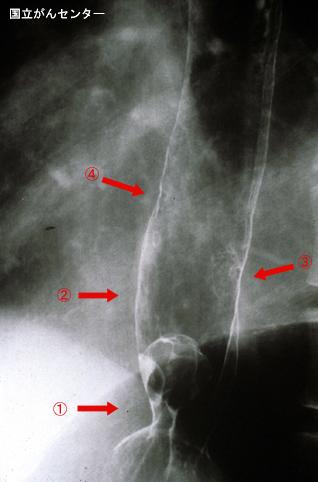

Múltiple Melanoma Maligno de Esófago acompañado de metástasis intramural

[Image-ID:4133]

Melanoma Maligno/

esófago/inferior

Rayos X

Tipo 0(tipo superficial)/Tipo I(Isp)

20 - 24

sm

múltiples tumores(en un mismo órgano)

presente(simultáneo)